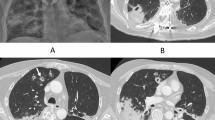

Allogeneic HCT recipients with IA due to azole-resistant Aspergillus spp. present clinically similar to patients infected with non-resistant strains, usually with a pulmonary infection, followed by sinusonasal and cerebral IA [115]. Rapid detection of azole resistance is fundamental, since infections caused by these strains are associated with higher mortality, between 88 and 100% [116, 117, 118]. Comparative studies between azole resistant and susceptible strains of Aspergillus spp. in IA showed a 21–31% higher mortality in the azole resistant group [116, 119]. As already mentioned, phenotypic diagnostic tests that require culture growth often miss “cryptic” species and the rate of culture-positivity varies between different patient groups [120, 121]. Clinical suspicion for resistant Aspergillus spp. should be rapidly raised in the context of a lack of clinical and biological (e.g., persistence of high galactomannan plasmatic levels) response to the administered therapy.